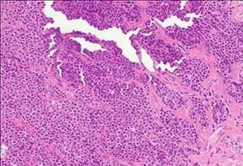

A 15-year-old male presents with deep knee pain awakening him at night. Radiographs show a permeative destructive lesion in the distal femoral metaphysis with a 'sunburst' periosteal reaction and Codman's triangle.

Biopsy confirms high-grade conventional osteosarcoma. What is the most critical prognostic factor for long-term overall survival in this patient?

Explanation

For localized high-grade osteosarcoma, the most important prognostic indicator is the histologic response to neoadjuvant chemotherapy. This is evaluated during the definitive resection. A 'good response' is typically defined as greater than 90% or 99% tumor necrosis. Patients who achieve this level of necrosis have a significantly improved disease-free and overall survival rate compared to 'poor responders' who have extensive viable tumor cells remaining.